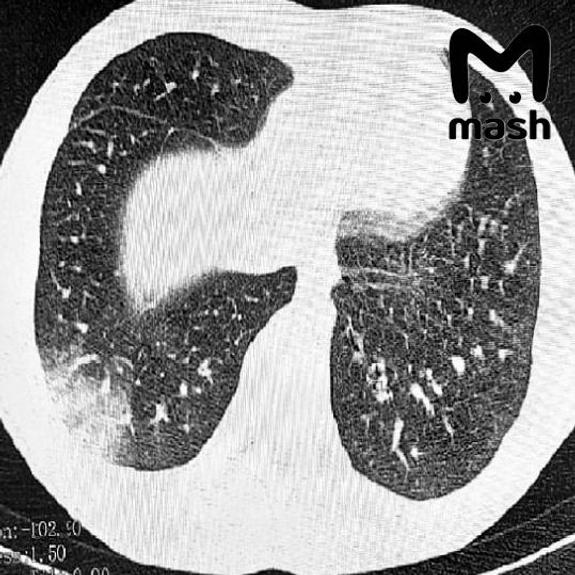

У 16-летнего пациента — серьёзная дыхательная недостаточность, потребовалась искусственная вентиляция лёгких. У другого — двусторонняя вейп-ассоциированная пневмония EVALI, врачи сделали операцию. Похожие случаи фиксируют и в других регионах России: первые в Москве в 2021-м, затем в Томске, где в прошлом году пострадали двое несовершеннолетних.

Врачи говорят: электронки серьёзно портят здоровье. Жидкости в дуделках содержат химические вещества, которые повреждают дыхательные пути, вызывают воспаление лёгких и приводят к проблемам с дыханием.